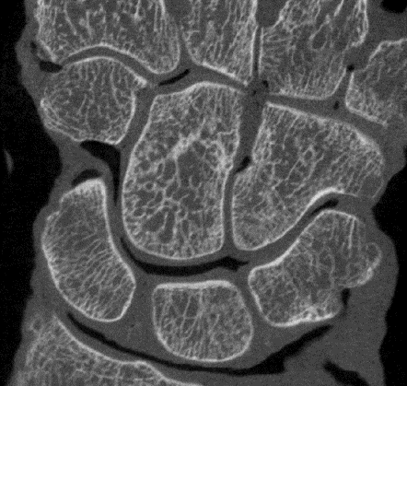

Obtaining high-resolution CT scans for clinical applications is challenging, However, it could help better understand and treat such bone diseases as osteoporosis. High-resolution peripheral computed tomography (HR-pQCT) is considered the best technique in vivo. However, a breakthrough for clinical practice is lacking due to a relatively long acquisition time, which inhibits scanning of large field of view (FOV) in vivo. A promising alternative is the high-resolution cone-beam computed tomography (CBCT), which is already the gold standard in many dental and maxillofacial applications. The top high-resolution CBCT scanners on the market (eg., Newtom 5G) feature a fast scanning time (18 à 31s), a large FOV (12x12x8cm3) and a low radiation dosage, in addition to a high resolution (voxel size down to 75µm). Yet, CBCT is impaired by the presence of image artefacts that reduce image contrast, leading to it being currently used for qualitative evaluation only.

To determine whether CBCT can be enhanced by means of artefact correction algorithms and advanced segmentation techniques in order to be used to visualize and quantify both bone microstructure and mechanical parameters in clinical practice.

CBCT enables fast scanning of large FOV of extremities at high spatial resolution. In addition, the enhanced CBCT images had a very comparable accuracy with HR-pQCT when quantifying bone microstructural and mechanical parameters. When enhanced, high-resolution CBCT is an attractive and promising imaging tool that can be used in the clinical treatment of several bone and joint diseases.

Mys K, Varga P, Gueorguiev B, Hemmatian H, Stockmans F, van Lenthe GH. Correlation between cone-beam computed tomography and high-resolution peripheral computed tomography for assessment of wrist bone microstructure, J Bone Miner Res. 2019,34:867-874